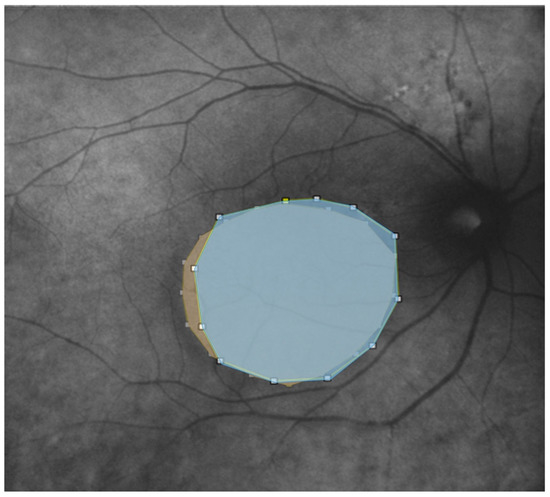

Figure 4.

Autofluorescence and Retromode overlaid on top of each other with different colorization (light blue for autofluorescence; yellow for retromode) and transparency to show the differences after using the caliper tool in ImageJ. The pseudo 3D effect of Retromode imaging clearly highlights the outline of serous neuroepithelium detachment in comparison with autofluorescence.

We further evaluated the extent (area expressed in mm2) of the disease features in AF, RM, and enface scans using ImageJ 1.8.0_345 software (ImageJ 1.53 k, National Institutes of Health, Bethesda, MD, USA) (Figure 3 and Figure 4). First, each image was converted to 8 bits, and the scale was set according to the size of the scan in millimeters, which was then converted into pixels. Then, we manually outlined the region of interest (ROI) with the provided caliper tool, and the software provided the area of the ROI. The ROIs were manually selected by two co-authors. A retinal specialist checked the segmented regions once the images were collected. If all three operators agreed, the image was consequently included in the analysis. Cohen’s coefficient analysis was used to ensure a concordance of at least 0.90. A neuroepithelium serous detachment was identified on the enface images as a hyporeflective area; within the enface images, it usually appeared isoautofluorescent. The pseudo-3D effect of retromode imaging helped to outline the detached area. RPE atrophy appeared as hyper- or hypoautofluorescence on AF with hyperreflective areas on enface imaging and mottling on RM imaging.